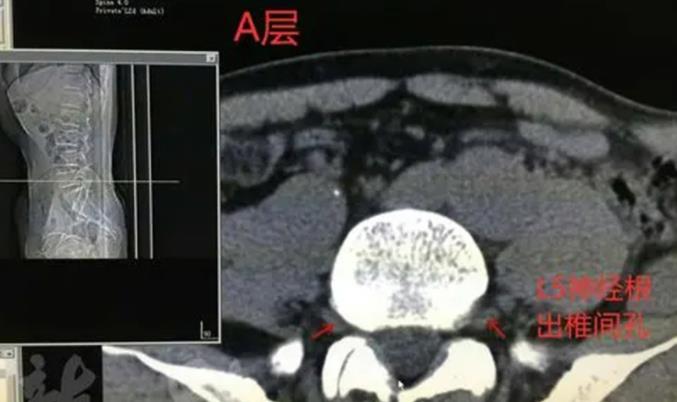

我今年57 岁,阵发性会阴区刺痛疼痛3个月,前来就诊。静息时发作明显,劳累可使症状加重,甚可伴排尿困难,休息平躺时也可能诱发会阴区刺痛。然后去医院检查,结果查出骶管..